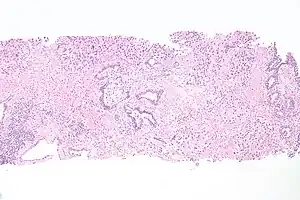

The cells lining the urethra (the epithelium) start off as transitional cells as it exits the bladder, which are variable layers of flat to cuboidal cells that change shape depending on whether they are compressed by the contents of the urethra.[12] Further along the urethra there are pseudostratified columnar and stratified columnar epithelia.[12] The lining becomes multiple layers of flat cells near the end of the urethra, which is the same as the external skin around it.[12]

Cancer can also develop in the lining of the urethra.[18] When cancer is present, the most common symptom in an affected person is blood in the urine; a physical medical examination may be otherwise normal, except in late disease.[18] Cancer of the urethra is most often due to cancer of the cells lining the urethra, called transitional cell carcinoma, although it can more rarely occur as a squamous cell carcinoma if the type of cells lining the urethra have changed, such as due to a chronic schistosomiasis infection.[18] Investigations performed usually include collecting a sample of urine for an inspection for malignant cells under a microscope, called cytology, as well as examination with a flexible camera through the urethra, called urethroscopy. If a malignancy is found, a biopsy will be taken, and a CT scan will be performed of other body parts (a CT scan of the chest, abdomen and pelvis) to look for additional metastatic lesions.[18] After the cancer is staged, treatment may involve chemotherapy.